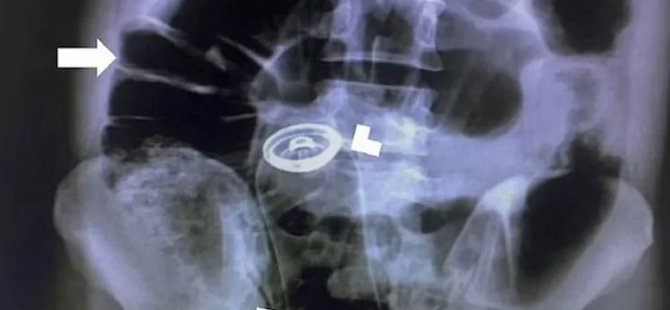

Durumu inceleyen doktorlar herhangi bir kanama ya da kesik olmadığı için genç adama röntgen çektirdi. Röntgen sonuçlarını inceleyen bilim insanları ise resmen şaşkına döndü. Adamın anüsünden içeri bir deodorant şişesi sokulduğunu ve röntgende şişenin iç organlara dayandığı görülüyor.

Röntgen sonucunda şişeyi gören doktorlar hemen harekete geçti.

Hemen ameliyat kararı alan doktorlar, adamın karnını keserek büyük boy deodorant şişesini aldı. Operasyonun iki saat sürdüğü belirtilirken, deodorant kutusunun nasıl girdiği ise açıklanmadı. İsmi açıklanmayan hastanın vakası “Visual Journal of Emergency Medicine” isimli tıp dergisinde yer aldı.